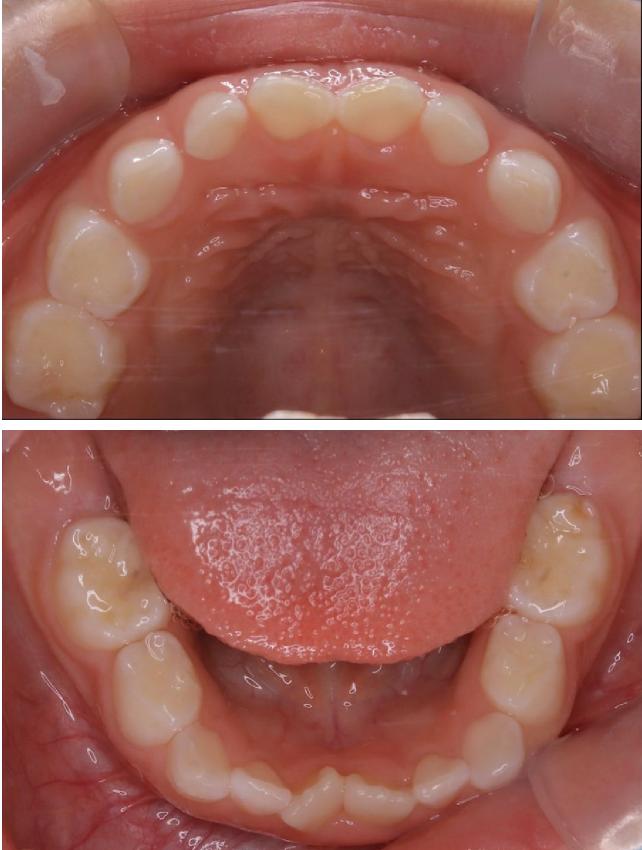

当院の症例

CASE